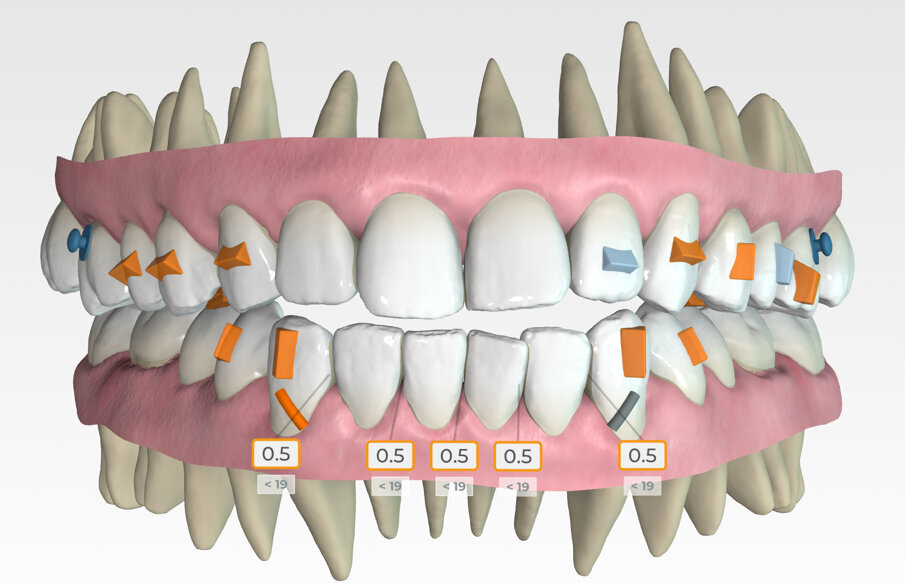

Specifically, the plan prescribed upper arch expansion and bilateral molar and second premolar intrusion of 3 mm. To support intrusion and prevent reciprocal lifting of the aligners, 4 mm wide occlusally beveled retentive attachments were designed and placed on the premolars. (Fig. 11)

Button cut-outs were prescribed on the upper first molars, and elastic hooks on the lower canines to attach 5/16, 4.5-ounce Class III inter-arch elastics. (Fig. 12)

Lower arch expansion and interproximal reduction of 0.5 mm were prescribed on all of the lower incisors from mesial of canine to mesial of canine before the 19th aligner. (Fig. 13) IPR would allow retraction to assist the Class III elastic correction of the negative overjet. Additionally, since counterclockwise autorotation of the mandible would project the lower incisors anteriorly, retraction would also assist in mitigating this effect.

Retraction and uprighting of the lower incisors would also achieve relative extrusion, further assisting in the closure of the anterior open bite. (Figs. 14,15)